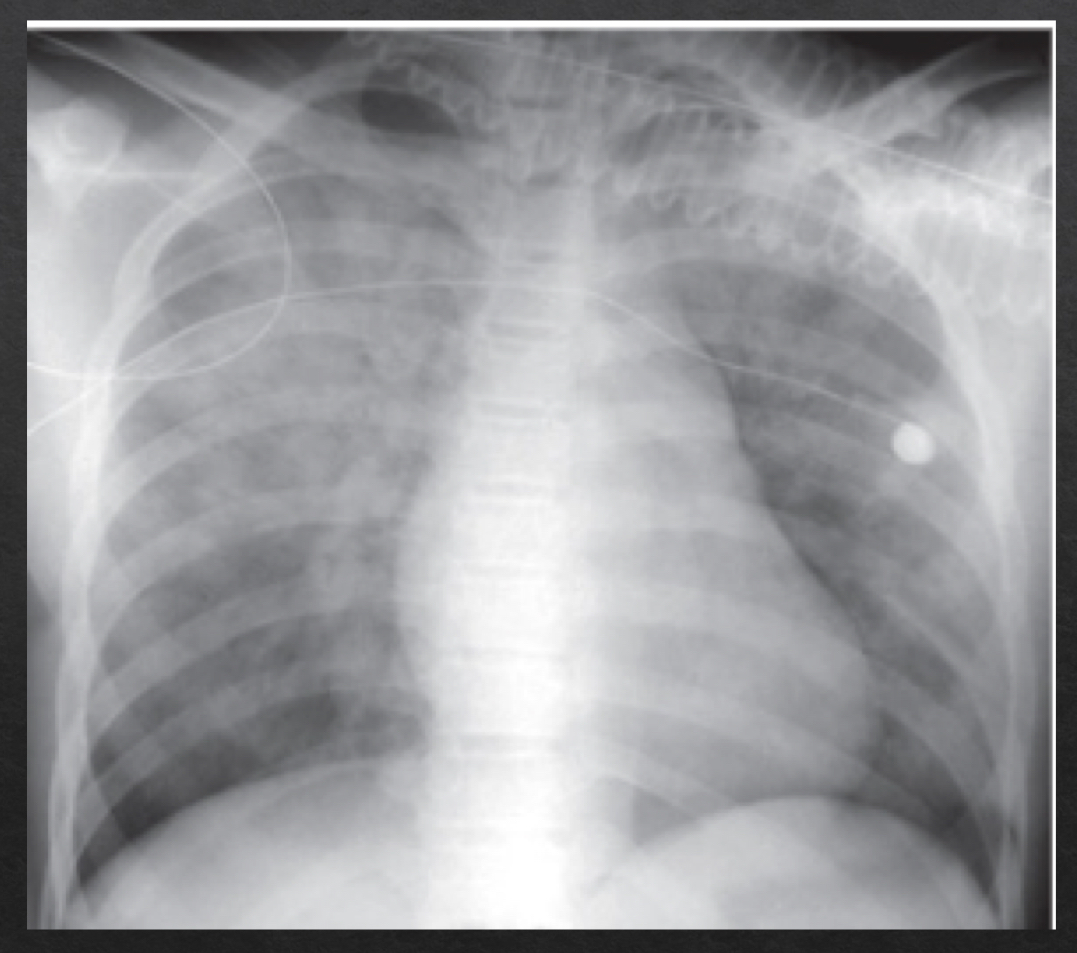

views of a chest X-ray

frontal

posteroanterior (PA)

anteroposterior (AP)

lateral

left lateral

technical adequacy of chest xray

PRIMA

Penetration

Rotation

Inspiration

Magnification

Angulation

penetration of chest xray

degree to which xrays have passed through the body

adequate penetration:

outline of the thoracic spine visible through heart

inadequate penetration

can mimic or hide disease

underpenetrated vs overpenetrated CXR

fills lungs adn contracts diaphragm

10 posterior ribs are visible above diaphragm

8-9 in hospitalized pts

suboptimal inspiration

compress and crowd the lung markings at the llung bases adn diaphram

could be misleading of pneumonia or cardiomegaly

only 7 posterior ribs visible

adequate rotation: spinous processes are equidistant btwn the medial ends of the clavicle

severe rotation findings

trachea appears shifted from midline (black arrow)

left lung appears much larger, right lung appears smaller

heart contour appears changed

left hemidiaphragm appears raised (white arrow)

plays a role in assessing heart size

closer an object is to the surface on which it is being imaged, the more true to actual size the resultant object will be

PA view is more true to size

farther away → more magnified

AP view

orientation of xray beam passing through object

views:

horizontal- normal

parallel to floor

medial end of the clavicle superimposes on 3rd or 4th rib

over angulated

bedridden pts that cannto fully sit up

clavicles are projected above first rib